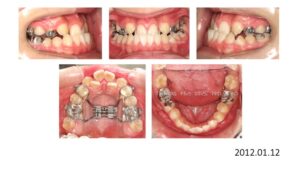

8歳の時、I市の歯科医院で、顎が狭くて歯が入りきらない、顎を拡げなければいけないといわれ、治療を開始したそうですが、6年経っても治療が終わらないどころか、写真のように全く噛み合っていないために、14歳の時にセカンドオピニオンで ひろ矯正歯科に来られました。

臼歯関係は、右が 4㎜ II級。左が 7㎜ II級で、7番しか咬合しておらず、著しい開咬を呈していました。

これは、拡大を始める前の写真ですが、口腔内写真を見る限り、拡大する必要はないです。

8歳からリンガルアーチで拡大を開始し、3年間拡大を続け、12歳でマルチブラケットを付けて治療を開始したそうですが、開咬が治らないためにアンカースクリューを4本打って治療を続けたとのことです。

こんなスクリューじゃあ何の意味もありません。

まさにやっている事がデタラメです。

ひろ矯正歯科に来られた時には、口腔内清掃状態は悪く、全ての歯が齲蝕でボロボロ、要治療でした。

治療中はブラッシング指導は一切無かったそうです。